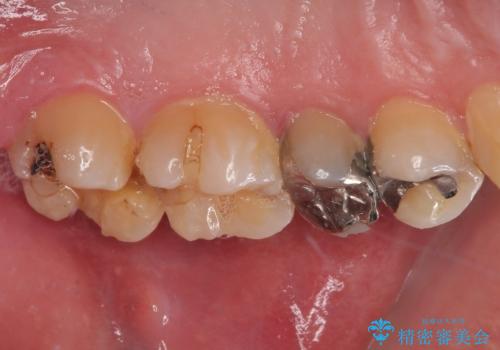

拡大鏡視野下で、金属の詰め物(メタルインレー)、虫歯の除去を行い、オールセラミッククラウンに適した形に整えました。

仮歯の状態で1週間ほど過ごしてもらい、歯茎の状態を健全な状態にしてから

歯と歯茎の間に圧排糸と言われる糸を入れてシリコーン印象材にて型どりをしました。